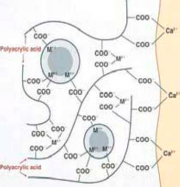

| 09:04, 18 ביוני 2013 | איטומי חריצים4.png (קובץ) |  |

111 קילו־בייטים | Motyk | 1 | |

| 08:57, 18 ביוני 2013 | איטומי חריצים3.png (קובץ) |  |

124 קילו־בייטים | Motyk | 1 | |